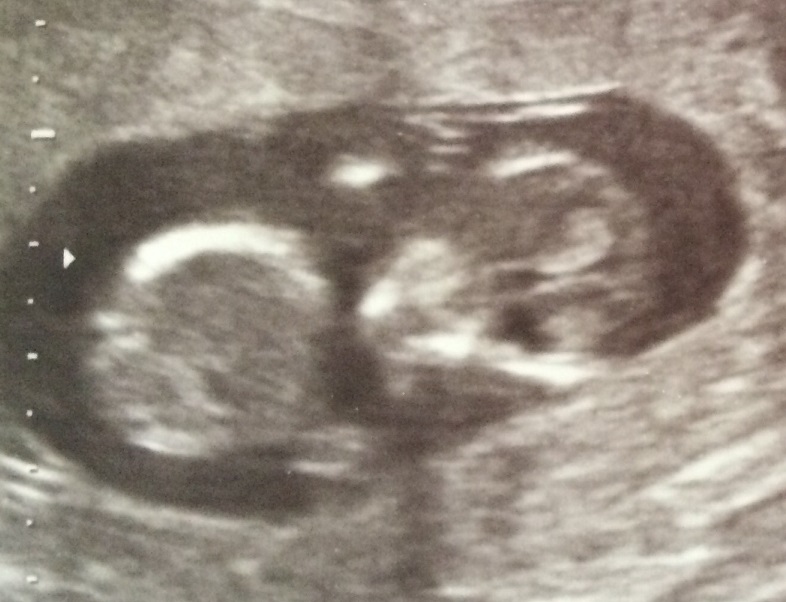

12 weeks + 3 days

The first hurdle is over; our official 12 week scan was this morning & we made it through.First things first, this baby is a wiggler! It didn't stay still ONCE the entire scan - and that meant the doctor had trouble getting decent pictures for us. Ah, baby.

The little one is 5.9cm long now and right on schedule for dates. Two arms, two legs, a spine, a big old brain, bladder and stomach - and a nuchal fold measurement of 1.39. I also have an anterior placenta, which is a bit of a bummer in terms of movement potential - but one day at a time!

Check out that giant head!